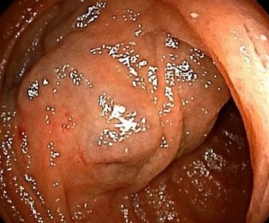

Endoscopic view of multiple gastric stromal tumors after suctioning of hemorrhagic products (Courtesy Dr. V. Penopoulos)